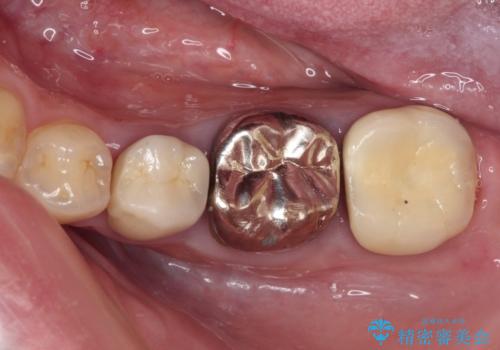

- 他院で抜歯矯正を終えた後、銀色の目立つ奥歯を白くしたいとのことで来院された患者様です。

既にセラミッククラウンが装着されている歯もありますが、不自然な色合いや黒い縁も気になるので、一斉に補綴治療をして統一感を持たせることとしました。